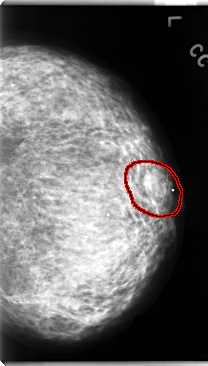

C_0130_1.LEFT_MLO

FILE: C_0130_1.LEFT_MLO.OVERLAY

TOTAL_ABNORMALITIES 1

ABNORMALITY 1

LESION_TYPE MASS SHAPE IRREGULAR MARGINS ILL_DEFINED

ASSESSMENT 4

SUBTLETY 1

PATHOLOGY MALIGNANT

TOTAL_OUTLINES 1

BOUNDARY